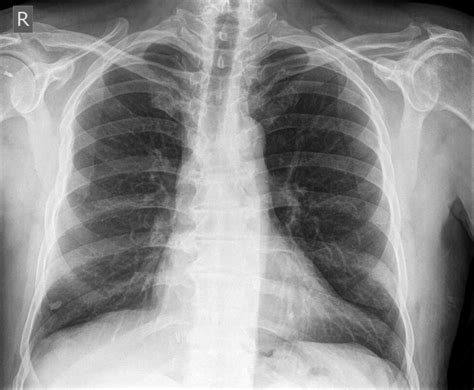

• Chest X-ray: This is often the first step in detecting lung nodules, but it has limitations in terms of detail and sensitivity.

When evaluating pictures of lung nodules, radiologists look for specific characteristics that can indicate the nature of the nodule. These characteristics include:

• Size: Larger nodules are more likely to be malignant.

• Shape: Irregular or spiculated edges are often associated with cancer.

• Density: Solid nodules are more concerning than ground-glass nodules.

• Growth Rate: Rapidly growing nodules are more likely to be malignant.